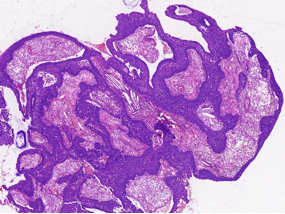

1、内翻性乳头状瘤:乳头结构简单、圆形,巢中央常形成囊腔,细胞成分复杂,包括鳞状细胞、纤毛柱状细胞和杯状细胞,可通过分子检测及AFF2 免疫组化鉴别。

病理特征:宽薄乳头、 迷宫样内翻生长、单一肿瘤细胞形态、棘层松解、显著中性粒细胞浸润;

具有纤毛上皮帽